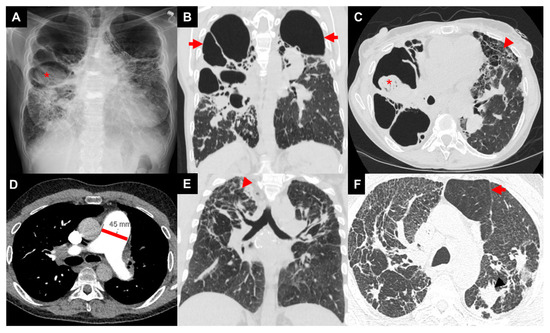

3.1. Imaging

- Abehsera, M.; Valeyre, D.; Grenier, P.; Jaillet, H.; Battesti, J.P.; Brauner, M.W. Sarcoidosis with pulmonary fibrosis: Ct patterns and correlation with pulmonary function. AJR Am. J. Roentgenol. 2000, 174, 1751–1757. [Google Scholar] [CrossRef]

- Criado, E.; Sanchez, M.; Ramirez, J.; Arguis, P.; de Caralt, T.M.; Perea, R.J.; Xaubet, A. Pulmonary sarcoidosis: Typical and atypical manifestations at high-resolution ct with pathologic correlation. Radiographics 2010, 30, 1567–1586. [Google Scholar] [CrossRef]

- Walsh, S.L.; Wells, A.U.; Sverzellati, N.; Keir, G.J.; Calandriello, L.; Antoniou, K.M.; Copley, S.J.; Devaraj, A.; Maher, T.M.; Renzoni, E.; et al. An integrated clinicoradiological staging system for pulmonary sarcoidosis: A case-cohort study. Lancet Respir. Med. 2014, 2, 123–130. [Google Scholar] [CrossRef]

- Nunes, H.; Uzunhan, Y.; Gille, T.; Lamberto, C.; Valeyre, D.; Brillet, P.Y. Imaging of sarcoidosis of the airways and lung parenchyma and correlation with lung function. Eur. Respir. J. 2012, 40, 750–765. [Google Scholar] [CrossRef] [PubMed]

- Sawahata, M.; Shijubo, N.; Johkoh, T.; Hagiwara, K.; Konno, S.; Yamaguchi, T. Honeycomb lung-like structures resulting from clustering of traction bronchiectasis distally in sarcoidosis. Respirol. Case Rep. 2020, 8, e00539. [Google Scholar] [CrossRef]

- Uzunhan, Y.; Nunes, H.; Jeny, F.; Lacroix, M.; Brun, S.; Brillet, P.Y.; Martinod, E.; Carette, M.F.; Bouvry, D.; Charlier, C.; et al. Chronic pulmonary aspergillosis complicating sarcoidosis. Eur. Respir. J. 2017, 49, 1602396. [Google Scholar] [CrossRef] [PubMed]